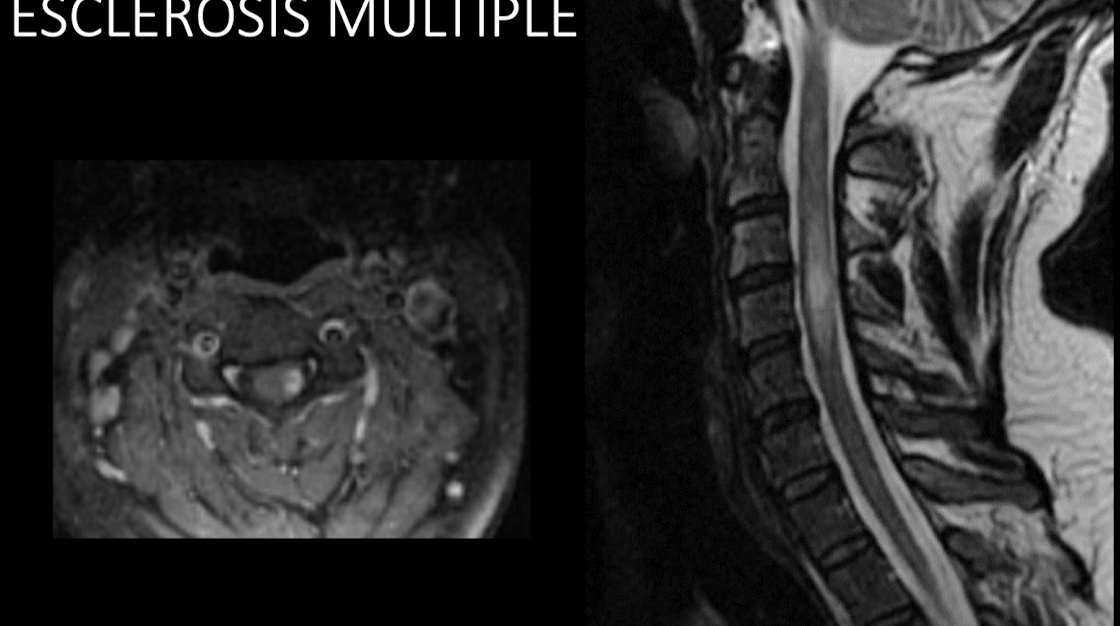

Variantes dx por RM

Devic, balo, marburg

Involucro a medula